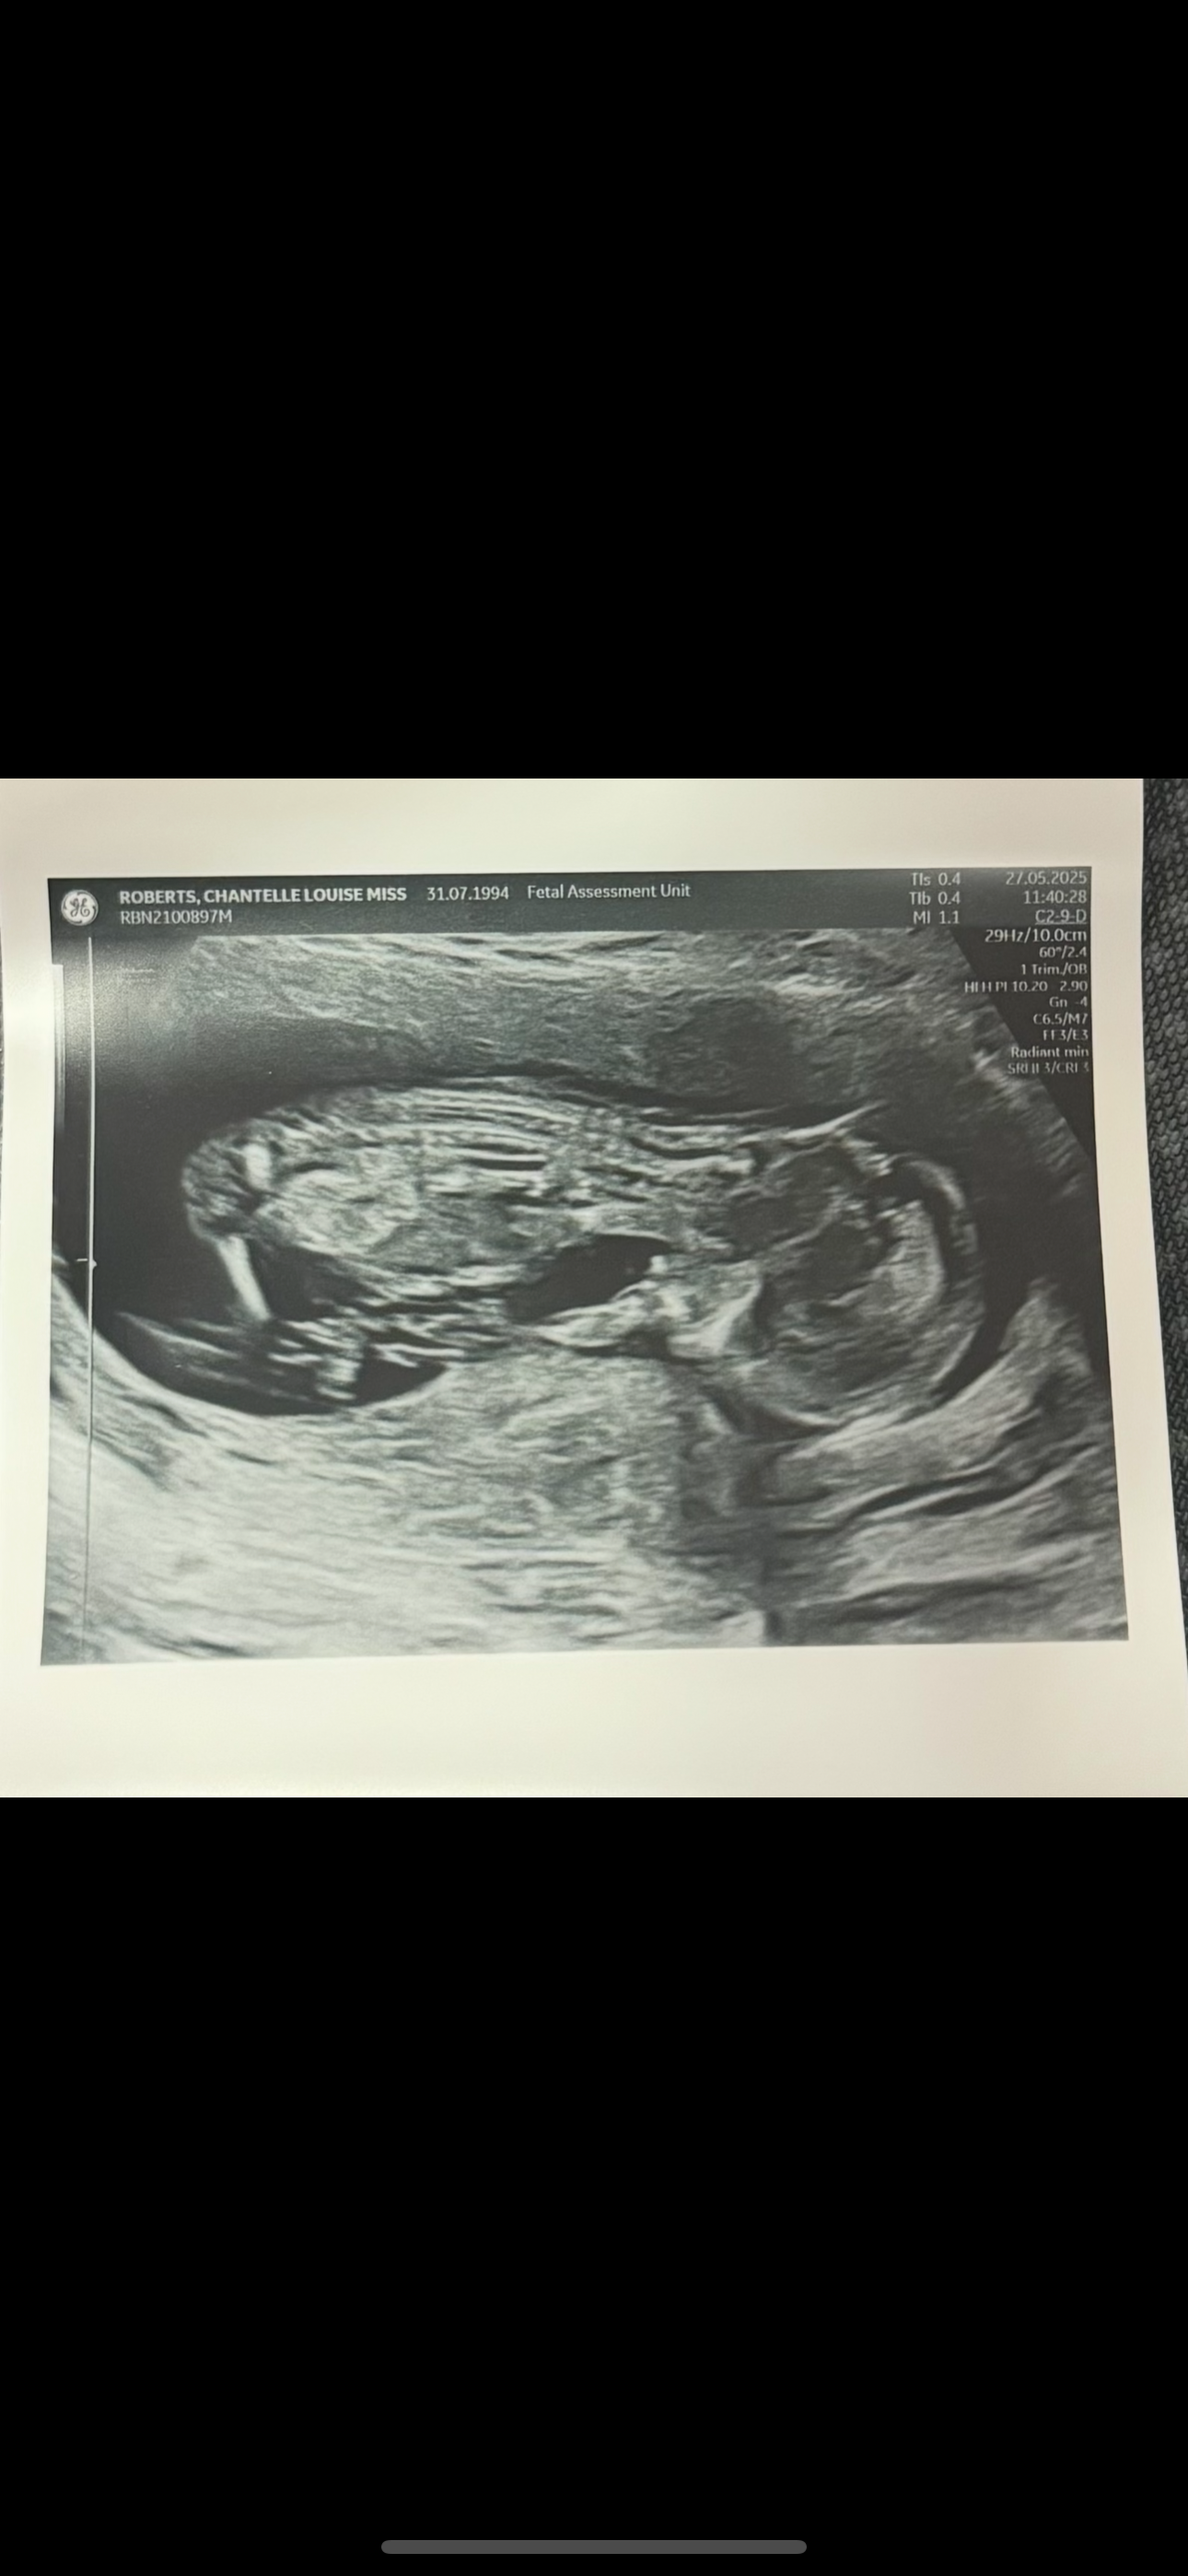

Hi my name is Chantelle.

me and my partner recently received some devastating news that our baby boy had no heartbeat and I gave birth to the most beautiful boy on the 18/06/2025 and his name is James Anthony Edward Devitt-Roberts!

what we have noticed in two of James scan pictures there is shapes off birds so it’s clear that James loved birds! In memory of our little boy we are looking to buy our very own bird and call him jimmy! We are hoping this go fund me will help us to buy all the things we need for James’s bird and anything we need for the bird as funds are tight right now!